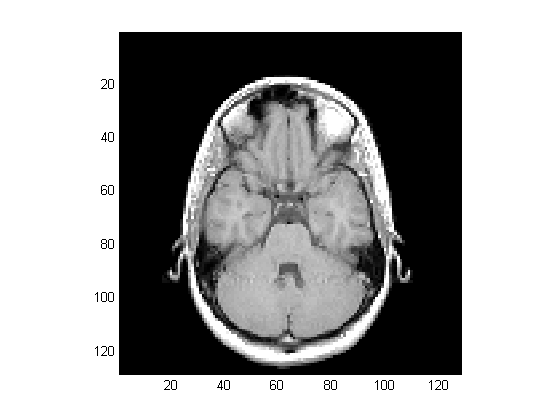

Displaying Images of MRI Data

To display one of the MRI images, use the image command:

figure('Colormap',map)

image_num = 8;

image(D(:,:,image_num))

axis image